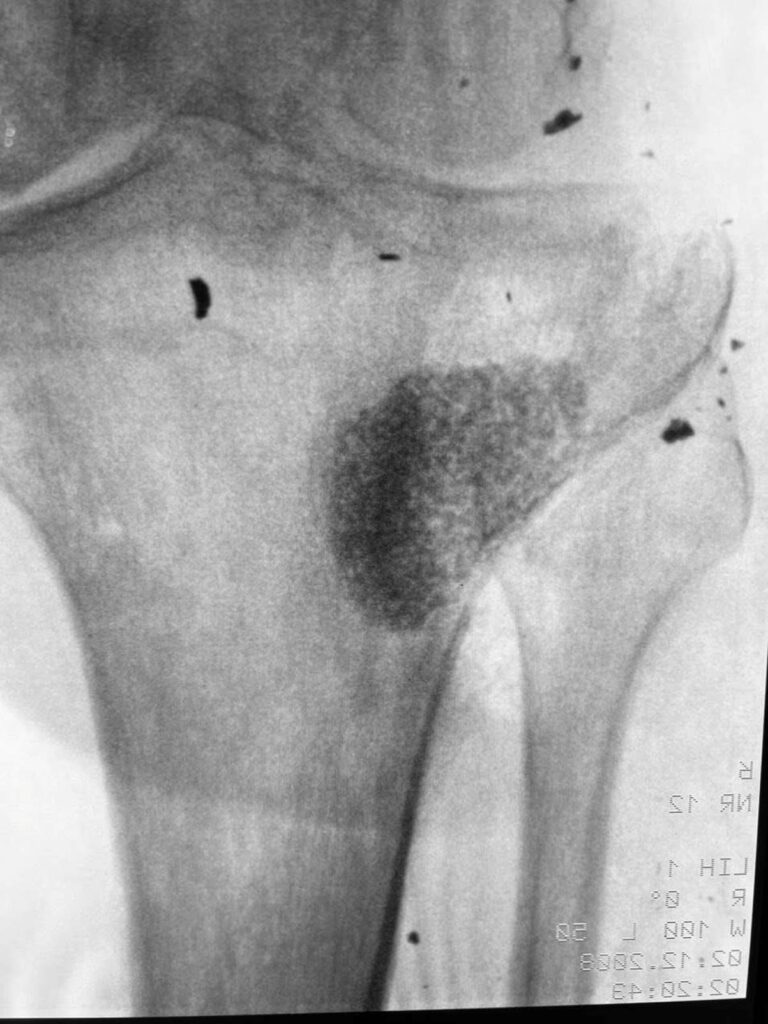

Тут вы видите рентгенограммы двух пациентов. В одном случае ранение голени у коленного сустава. В другом случае у сустава голеностопного с переломом костей. Поэтому там пластина еще стоит.

Обоим раненым (а каждый из них лечится по полгода уже) проведены по несколько операций дебридмента («чистка» кости и мягких тканей). К сожалению, это не остановило инфекцию.

В общем, все чаще и чаще приходится травматологам в Украине применять Bonalive. Это заменитель кости с антибактериальным действием. Только вот действует этот заменитель (финского производства) не за счет антибиотиков. Их в нем нет. А за счет того, что резко меняет Ph среды в кислую сторону. Бактерии погибают, привыкания к этому заменителю нет и быть не может (пока и если не появится какой-то новый, доселе неизвестный микроб), рост же собственной кости резко стимулируется.

Bonalive, как и всякий современный препарат высокотехнологичного производства, очень и очень дорог. Вот такой шприц-контейнер, как на фото, с 10 «кубиками» препарата стоит 500 евро (плюс-минус несколько процентов в зависимости от величины поставки).

Эти двое пациентов, чьи рентгенограммы вы видите, были прооперированы Председателем нашей Ассоциации AO Trauma Ukraine Олександром Рихтером в одном из военных госпиталей на западе Украины. Все зажило отлично.

Для первого раненого хватило 10 кубических сантиметров Bonalive, на второго – там, где пластина, ушло 20 «кубиков». Итого, в дополнение ко всему прочему – это 1500 евро.